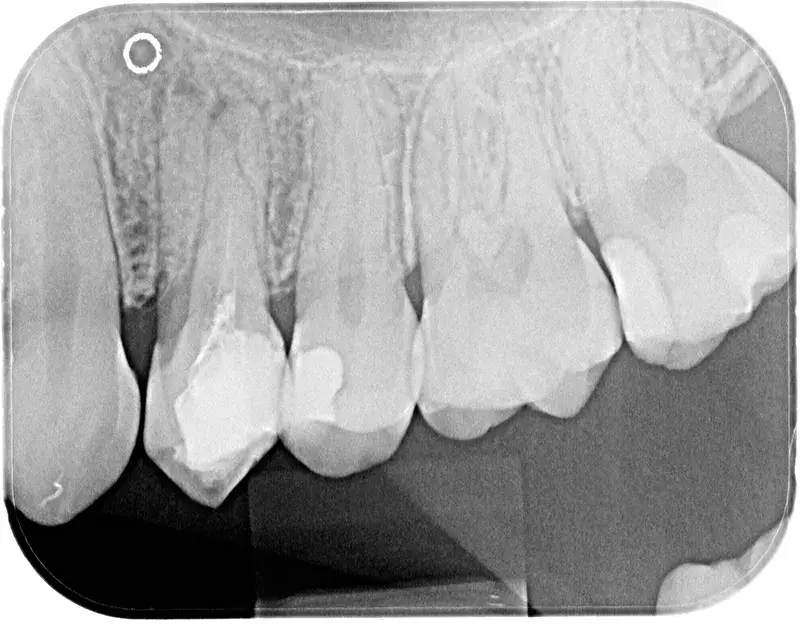

Das Ergebnis dieser Präzision machen wir für Sie sichtbar: Auf dem abschließenden Röntgenbild sticht eine gelungene Wurzelfüllung klar weiß hervor. Sie muss lückenlos bis zur Wurzelspitze reichen und darf keine Lufteinschlüsse aufweisen. Ein entscheidender Punkt dabei: Es müssen zwingend alle Hohlräume behandelt werden – und nicht nur drei von vier Kanälen. Da wir auf diese Behandlungen spezialisiert sind und einen eingetragenen Tätigkeitsschwerpunkt führen, konnten wir bereits viele Zähne retten, die anderswo als verloren galten.

Jeder Zahn ist so individuell wie ein Fingerabdruck. Normalerweise findet man bei diesem Zahntyp zwei Kanäle – in diesem speziellen Fall hat uns die Anatomie jedoch herausgefordert: Es waren drei!

Das Auffinden solch seltener Strukturen erfordert Geduld und Erfahrung. Wir freuen uns über dieses Ergebnis, denn nur eine lückenlose Reinigung und Füllung aller Kanäle schützt den Zahn dauerhaft vor neuen Entzündungen. Ein kleiner „Erfolgskrimi“, der zeigt, warum wir bei Wurzelbehandlungen keine Kompromisse machen.